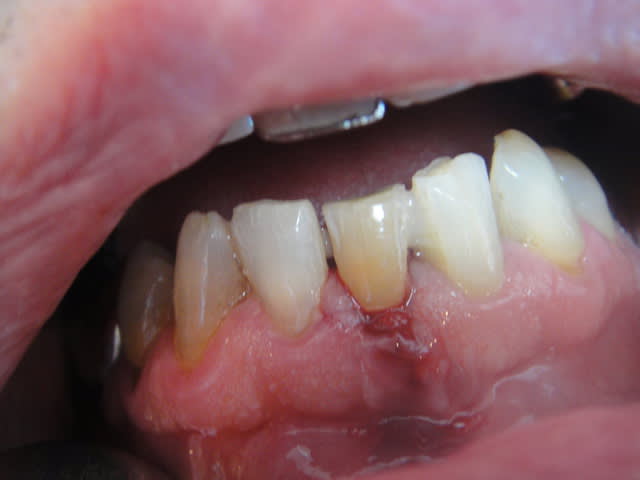

la suite pour blette que ça interesse .je suis agréablement surpris de la de la rétention et de la stabilité données par cs 2 pins dentinaires

photos lundi ou mardi scellé